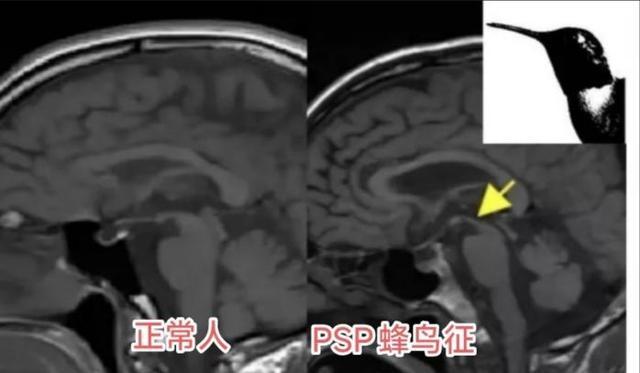

为了证实推断,医生调取了王大爷的脑部核磁共振图像。在脑干中脑部位的矢状位图像上,一个典型的特征出现了,熊猫体育官方中脑组织明显萎缩,侧面轮廓看起来就像一只蜂鸟的剪影。

它并非真的有一只鸟,而是中脑萎缩后,在影像上形成的特殊形态。正是这只“蜂鸟”,揭示了困扰老人三年的病根。